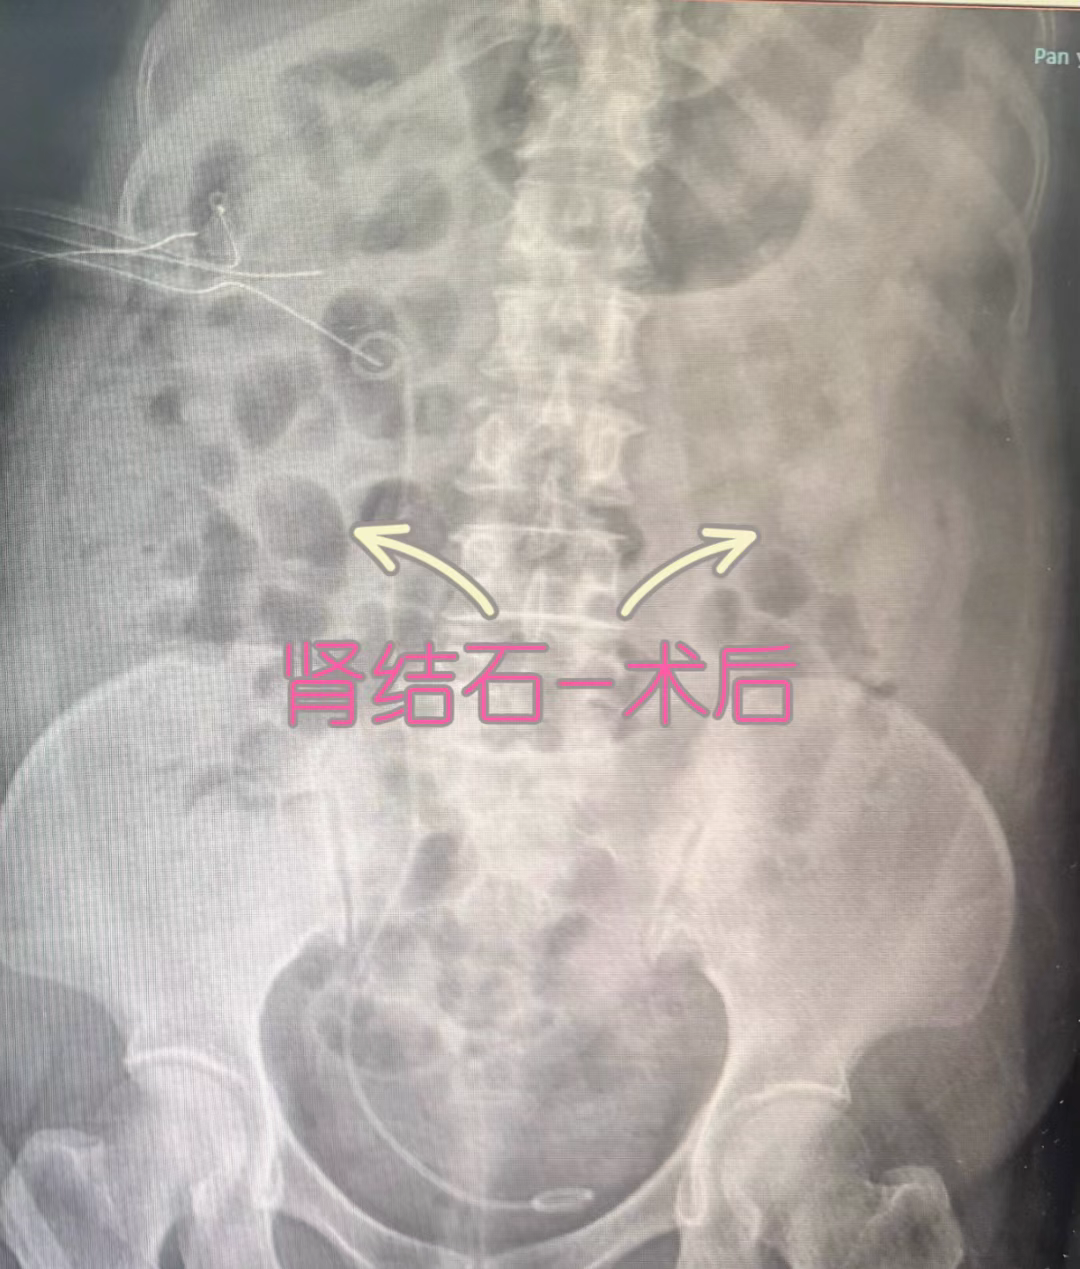

术前检查,结石几乎将整个肾盂肾盏都堵塞了。术后双肾结石被处理干净。

经过详细的检查和评估,医生发现,春姨的双肾多发结石已形成铸型结石,几乎将整个肾盂肾盏都堵塞了,还引起双肾积脓、肾功能不全等情况,病情严重。

面对如此棘手的问题,罗欣副主任医师手术团队和手术麻醉科团队进行了多次评估和讨论,最终为春姨制定了详细且相对安全的手术方案:采用小通道、多通道,控制出血的同时快速碎石取石。经过分期手术,右边7个通道,左边5个通道,总手术时间超过20小时,最终成功将阿姨的双肾结石处理干净,术后检查肾功能基本正常。